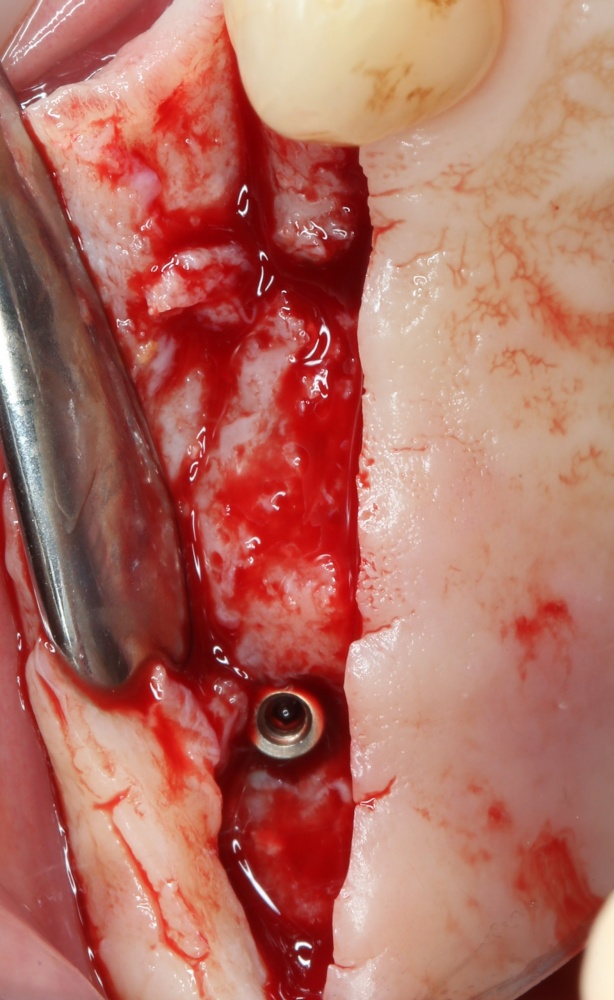

Прежде, чем приступить к аугментации (пластике) лунок зубов, мы подготовили лунки для имплантатов. В таких клинических случаях нет необходимости в использовании шаблона. Вместо этого, мы применяем общепринятые правила позиционирования и соблюдаем рекомендации производителя по хирургическому протоколу:

В процессе ирригации лунки промываются, что позволило нам еще раз подтвердить ранее сделанные выводы. С помощью аналогов имплантатов, входящих в хирургический набор Xive, мы проверили возможность стабилизации имплантатов в будущих лунках. Исходя из правил подбора и позиционирования имплантатов (я очень рекомендую почитать об этом здесь>>) мы остановились на Xive S диаметром 3,4 мм и длиной 13 мм.

Затем уложили ксенографт. Особенностями Bio-Oss Collagen являются удобство адаптации, устойчивость к вымыванию и выдавливанию, поэтому мы просто уложили полученные ранее пирамидки вестибулярно относительно будущего имплантата, после чего прижали их с помощью уже упоминавшихся аналогов имплантата, входящих в хирургический набор имплантационной системы Xive (кстати, при работе с другими имплантационными системами для паковки графта в лунке можно использовать круглые остеотомы для синуслифтинга).

Установка имплантатов

По ряду уже упомянутых выше причин, для решения этой клинической задачи мы выбрали имплантаты Xive. Лунки для них мы уже приготовили. возможную первичную стабильность оценили. Имплантаты мы установили с усилием чуть больше 15-20 Нсм — такого крутящего момента более, чем достаточно, особенно если учесть, что временные коронки будут соединяться между собой.

После перкуторной проверки стабильности имплантатов и точности позиционирования, мы переходим к следующему этапу — сохранению десневого контура.

Установка имплантатов занимает около двух минут.